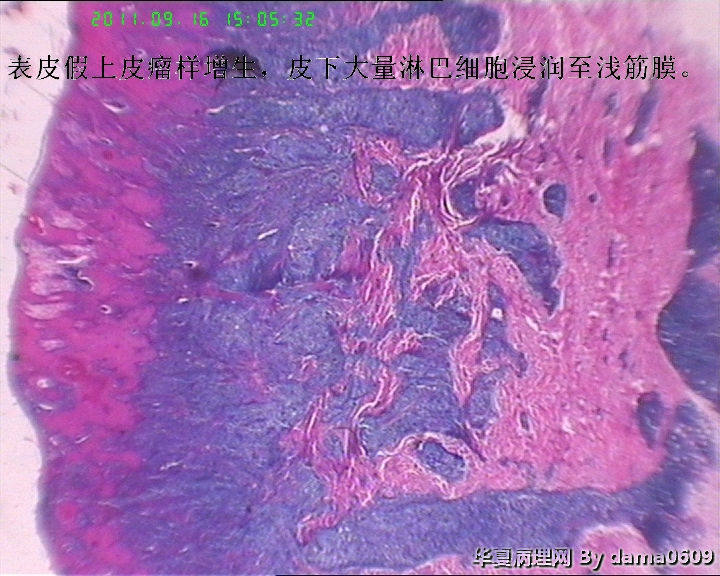

• 背部肿物,急请老师看看!!图3

图3

结合病史及镜下表现,如淋巴细胞浸润以皮下浅层为重、向下渐轻等,是否可符合书上的一个诊断:皮肤假性淋巴瘤(皮肤B细胞假性淋巴瘤)?学生自己没见过,还请老师多指教!!!谢!!

假上皮瘤样增生,其下大量淋巴样细胞浸润,结合有外用药病史,考虑急性淋巴细胞反应性增生。

图片欠清晰,大量淋巴细胞真皮、皮下组织浸润,好像异型性不是太明显?结合病史,不除外假性淋巴瘤。还是做个免疫组化为妥。